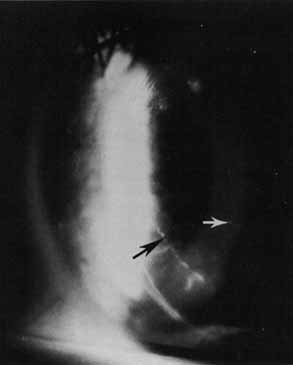

The current number of procedures performed on an annual basis is decreasing slightly; a total of 32,744 corneal transplants were performed in 2002, marking the first time since 1986 that the number of procedures performed has been less than 33,000.1 This downward trend has coincided with the decrease in incidence of pseudophakic corneal edema (PCE) (Fig. 1) and aphakic corneal edema (ACE). The percentage of PKs performed to treat PCE has dropped from 19.8% in 2001 to 18.4% in 2002, which was the lowest percent reported in this category in 15 total years of tracking by the Eye Bank Association of America (EBAA). It is possible that this decrease reflects improved cataract removal technique and technology, such as phacoemulsification and posterior chamber intraocular lens placement. The indications for PK have shifted over the past several decades, with PCE the most common indication since 1980, whereas keratoconus (Fig. 2) and ACE were the most common indications prior to 1980.2 Data is tracked for a total of 16 indications for transplant by the EBAA. Pseudophakic corneal edema, keratoconus (particularly in younger patients), Fuchs' endothelial dystrophy (particularly in older patients), and regrafting secondary to rejection or other reasons currently sit atop the list of indications for PK.

Fig. 1 Pseudophakic corneal edema is the leading indication for penetrating keratoplasty in the United States.